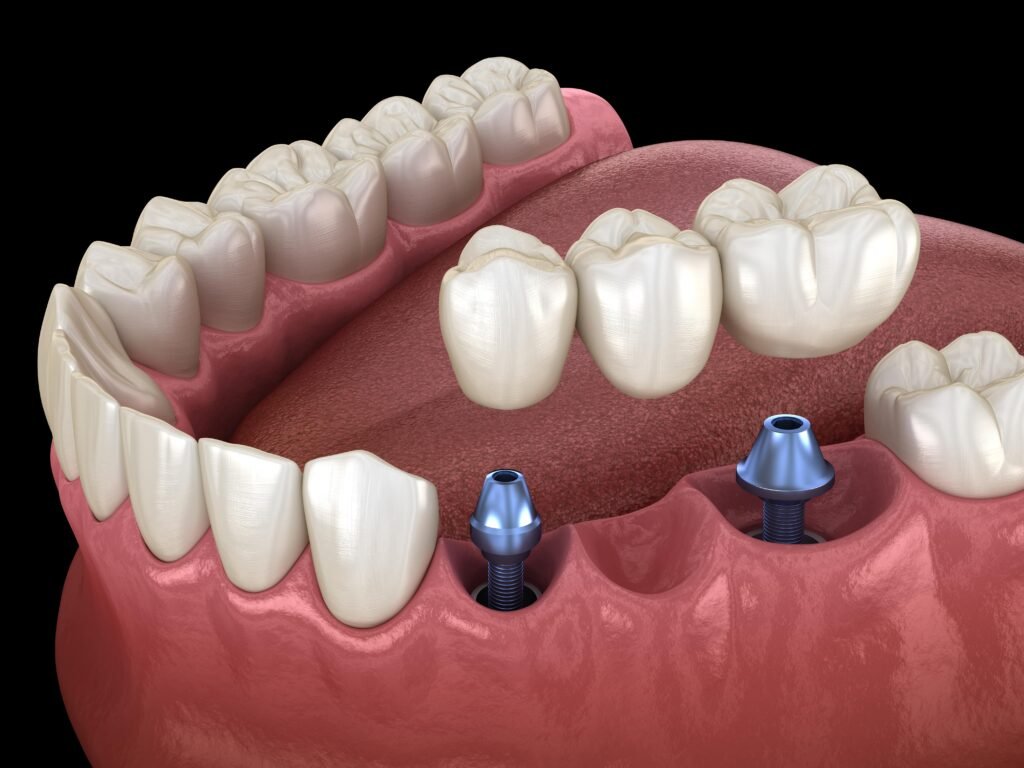

What Is Dental Implantology? Dental implantology is a modern dental discipline focused on replacing missing teeth using biocompatible titanium implants that integrate directly with the

What Is Dental Implantology? Dental implantology is a modern dental discipline focused on replacing missing teeth using biocompatible titanium implants that integrate directly with the

What Is Prosthodontics? Prosthodontics is the specialized branch of dentistry focused on restoring and replacing missing or damaged teeth using custom-made dental prosthetics. The goal